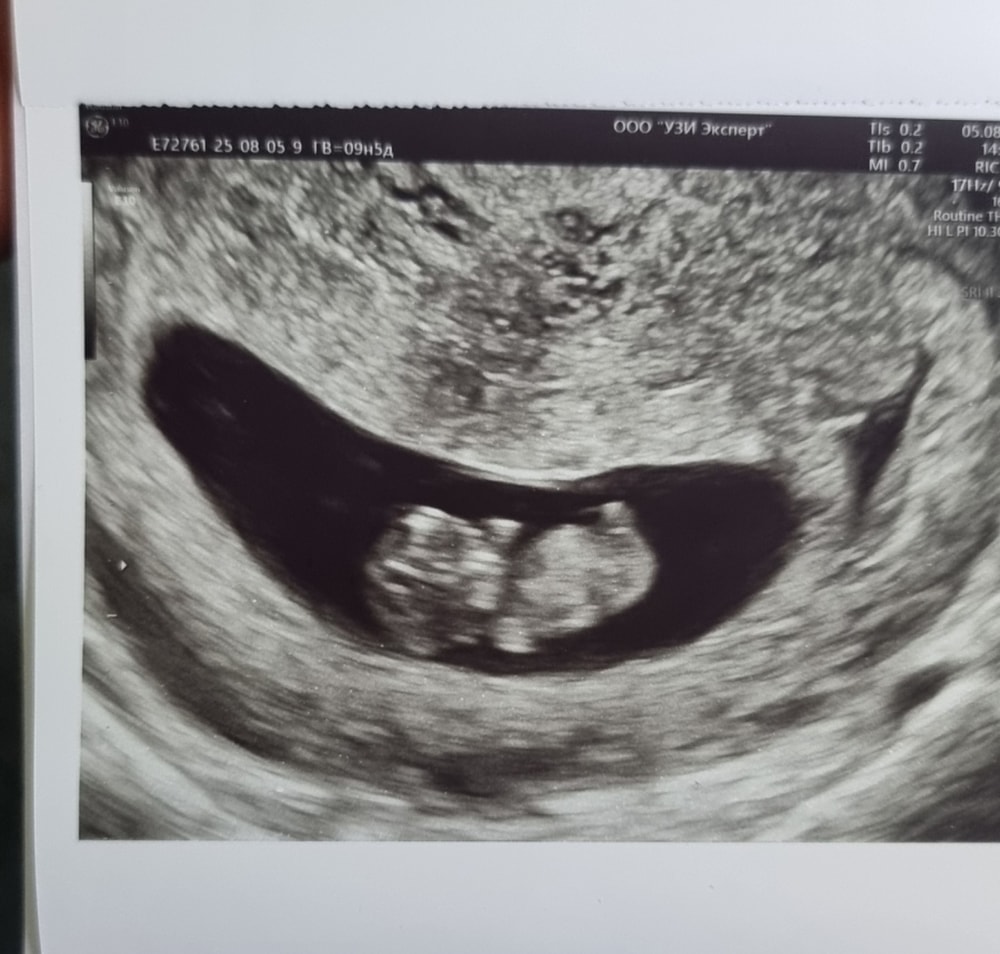

Добрый день! 5 Сентября сдала ХГЧ по просьбе врача на платной основе. Результат вышел 17045. Гинеколог бесплатной отделений говорит что на таком сроке 6 недель бесполезно сдавать ХГЧ. Как вы думаете? Извините пожалуйста что может задаю тупые вопросы. Но это первая беременность естественным путем в течений 7 лет и 2 неудачных эко. Раньше до этого 21 августа хгч был 219 и я в этот же день сходила на узи ПЯ был 2.7мм. Потом сдала ХГЧ 26 августа был 2629 и 28 августа 4044. 3 сентября ПЯ был 14.6 мм. Но нет сердцебиение. Срок был 6 нед 2 дня.

У меня к примеру при отслеженной овуляции на 31 дпо ктр 5 мм был с сб,пошла бы я на 28 дпо как автор был бы эмбрион 2 мм,если брать что он растет 1 мм в сутки,не факт что разглядели,а на 31 дпо пя 19 мм,ктр 5,на 28 дпо получается пя было б 16 мм,у автора 15 мм пя и жм 3,3 что соответствует ее сроку,не вижу здесь ничего критичного,чтобы ставить диагноз зб,большая вероятность что у нее уже сегодня есть эмбрион и сб,просто рановато пошла на узи